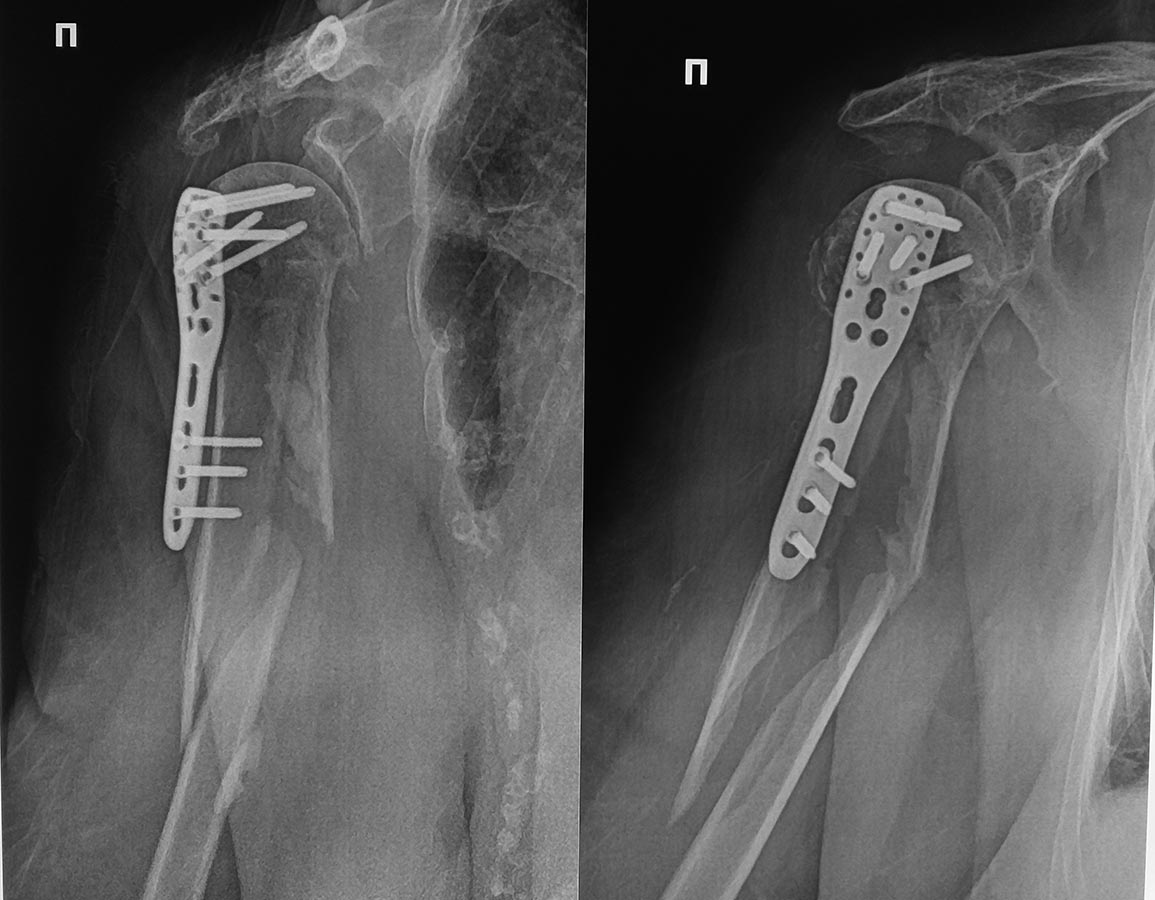

Пациентка Ф. 83 года поступила в клинику с оскольчатым переломом

хирургической шейки плеча. Через 7 дней с момента поступления выполнена

операция МОС. На 6-е сутки после операции падение в палате, результат

периимплантный перелом плеча.Что делать? МОС пластиной. стержнем или

консервативное лечение.